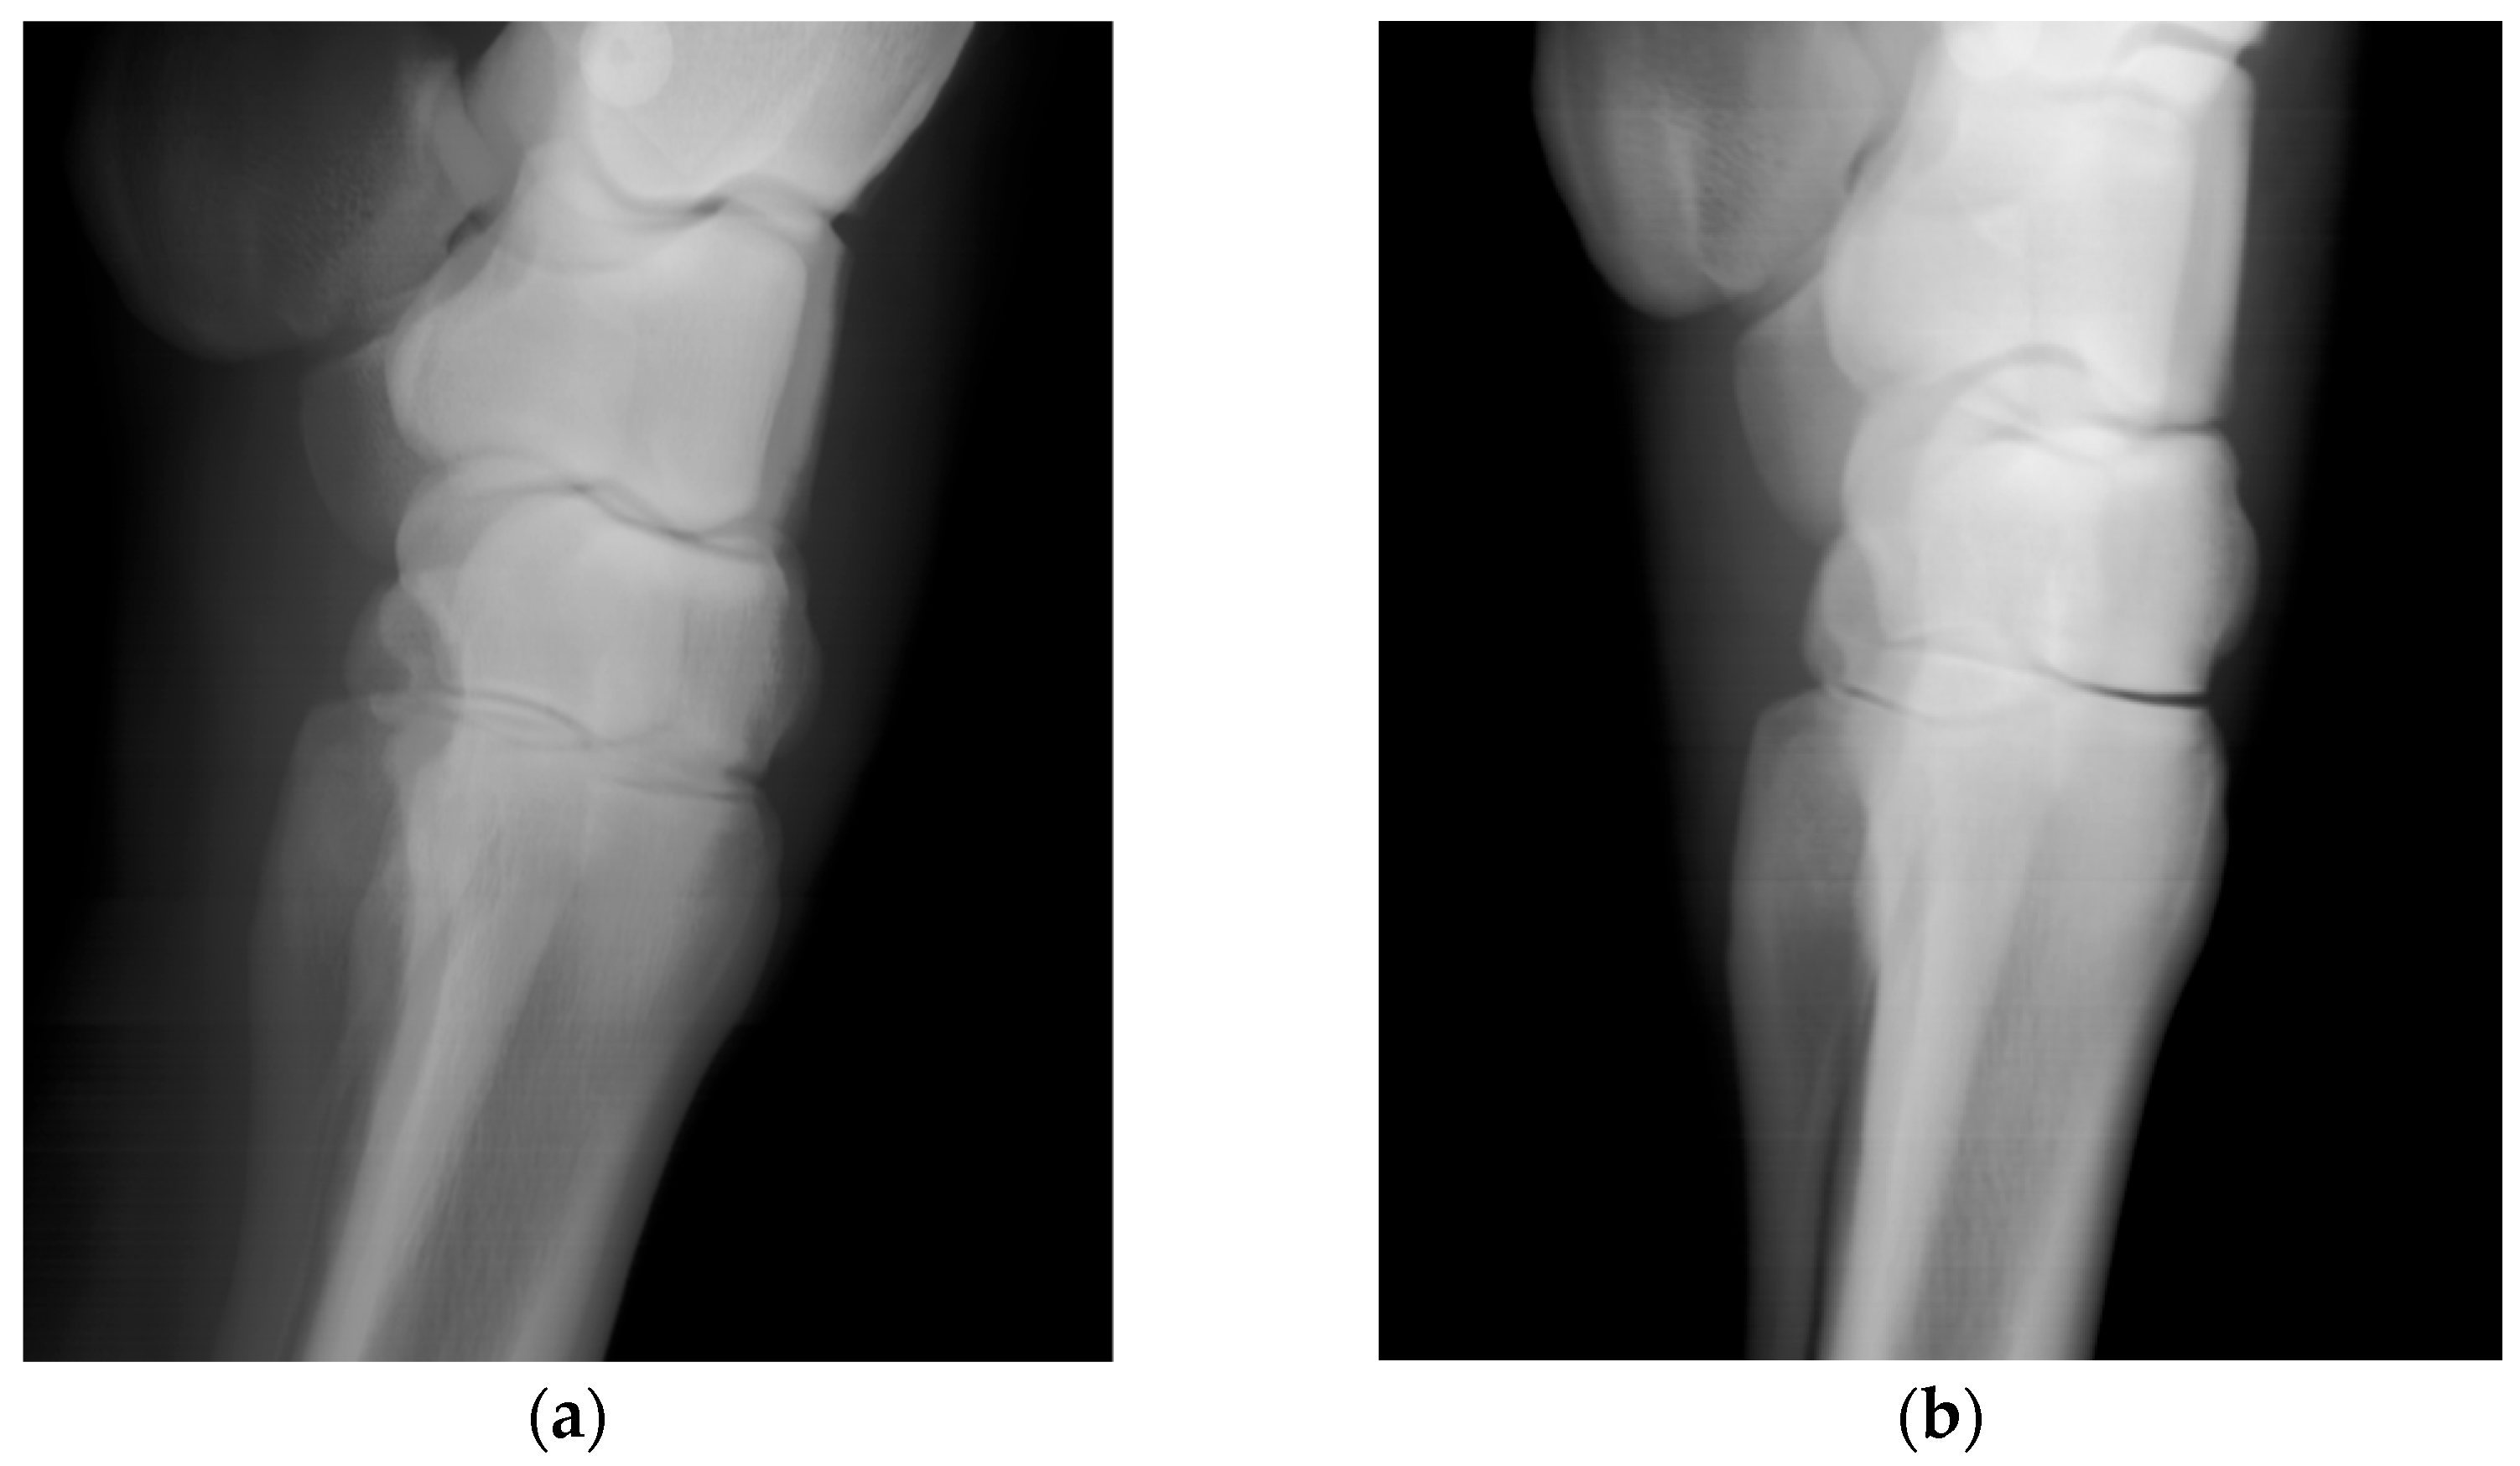

Scans of the horses’ distal forelimb, focusing on the hock and metatarsal, were performed utilizing the calibrated DH parameters. The images are clear and permit visualization of bone trabecular-level detail (Figure 5). For comparison, the second prismatic joint on the detector side’s θ parameter was returned to its initial value and an image of an equine lumbar segment phantom was collected (Figure 6). There is an obvious improvement in image sharpness with the calibrated system (Figure 6).

Figure 5. Lateral images of an equine carpus and metacarpus acquired in vivo from a standing horse, (a) acquired with 140 kVp and 12 mA source voltage and current technique and (b) acquired with a 70 kVp and 24 mA technique. For the 15 horses imaged, the beam was on for between 15 and 20 s.